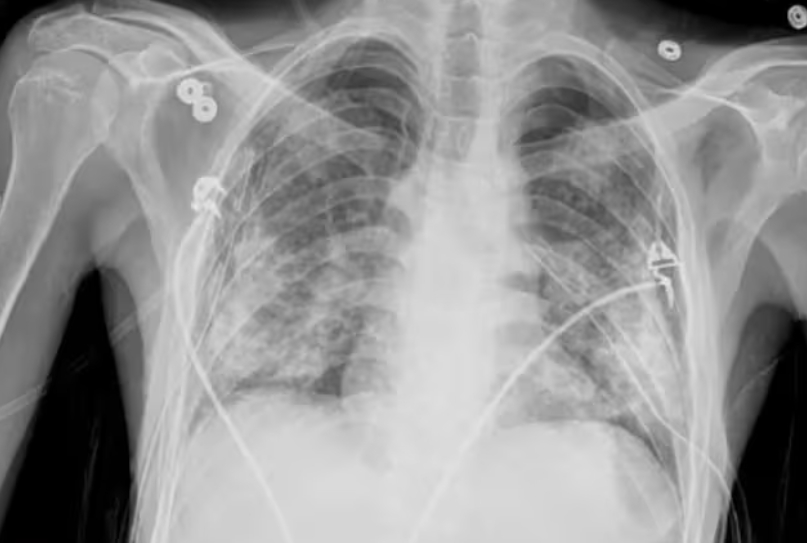

엑스레이는 가볍고 빠른 검사예요. 병원에서 기침이나 흉통이 있으면 가장 먼저 찍는 사진이죠. 하지만 엑스레이는 가슴 속 장기를 한 번에 찍기 때문에, 여러 구조가 겹쳐 보입니다. 그만큼 정확한 구분이 어렵고, 미세한 결절이나 염증은 지나치기 쉽습니다.

흉부CT는 이야기가 달라요. 얇게 자른 단면을 수백 장 촬영하기 때문에, 작은 병변도 놓치지 않습니다. 마치 산 전체를 한 장의 사진으로 보는 엑스레이와 달리, CT는 나무 한 그루 한 그루를 자세히 보는 느낌이에요. 예전에 병원에서 일했던 친구 말로는, 엑스레이에 아무 이상이 없던 환자가 CT에서 폐암 초기 진단을 받은 경우도 많았다고 합니다. 그만큼 CT는 정밀한 탐색 도구입니다.